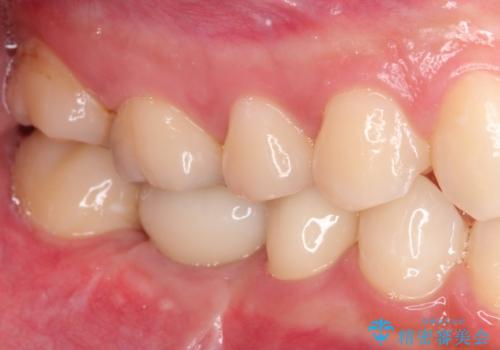

保存不可能な歯を抜歯してインプラント治療

見た目では問題がなさそうでも、レントゲン撮影・診査を行うと状態が悪くなっていることがあります。